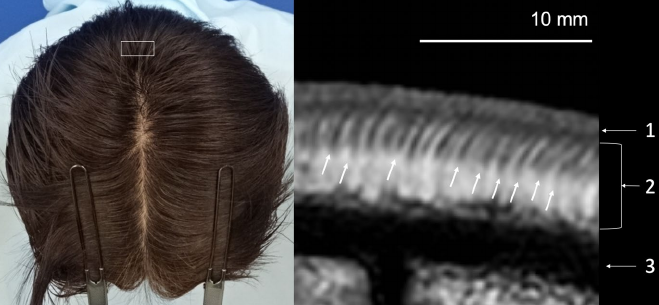

올해 초에 일본 연구진이 발표한 연구입니다. 27명을 탈모군과 대조군으로 나눠 두피를 MRI로 촬영한 후 두피의 진피, 피하층, 모낭 길이 등 탈모와 관련된 조직의 깊이를 측정했습니다.

결과는 위의 표와 같습니다. 탈모 환자들의 두피가 일반인들에 비해 많이 얇아지는데 특히 피하지방층이 타격을 많이 받는다는 결론입니다. 모낭 역시 크게 짧아지다 보니 탈모인의 모낭/피부 두께 비율이 크게 감소합니다. 피하지방층을 많이 채취하기 어려운 비절개 모발이식을 하다 보면 실제로 체감하는 현상입니다. 탈모 진행이 덜된 분들일수록 피부 조직 아래쪽으로 모낭이 길게 뻗어있을 가능성이 높습니다.

사실 그리 놀라운 결과는 아닌 것이 이미 탈모가 진행된 두피는 대조군에 비해 얇다는 연구가 잘 알려져 있었습니다. 다만 이 연구에서는 탈모가 많이 진행되더라도 진피까지의 두께는 거의 줄어들지 않고 대부분 피하지방층이 줄어든다는 점을 확인할 수 있습니다. 다른 연구들은 피부를 생검해서 병리 표본(샘플을 만드는 과정에서 피부가 수축할 가능성)을 만들거나 캘리퍼 등으로 피부를 집어서 두께를 측정(피부 특성에 따라 측정값에 오차가 발생)하는 방식을 측정했는데, 이 연구의 측정 방식이 피부 조직 그대로의 모습을 제일 잘 보여준다고 하겠습니다.

무엇보다도 이 연구는 MRI 촬영을 통해 객관적인 수치, 즉 모낭 길이와 피부 두께의 비율을 검사해서 탈모 진행 정도를 정량적으로 파악할 가능성이 생겼다는 점에서 특기할만합니다. 의사의 눈에 의존하지 않고 초기 탈모에서도 비교적 정확한 진단이 가능해지기를 바랍니다.